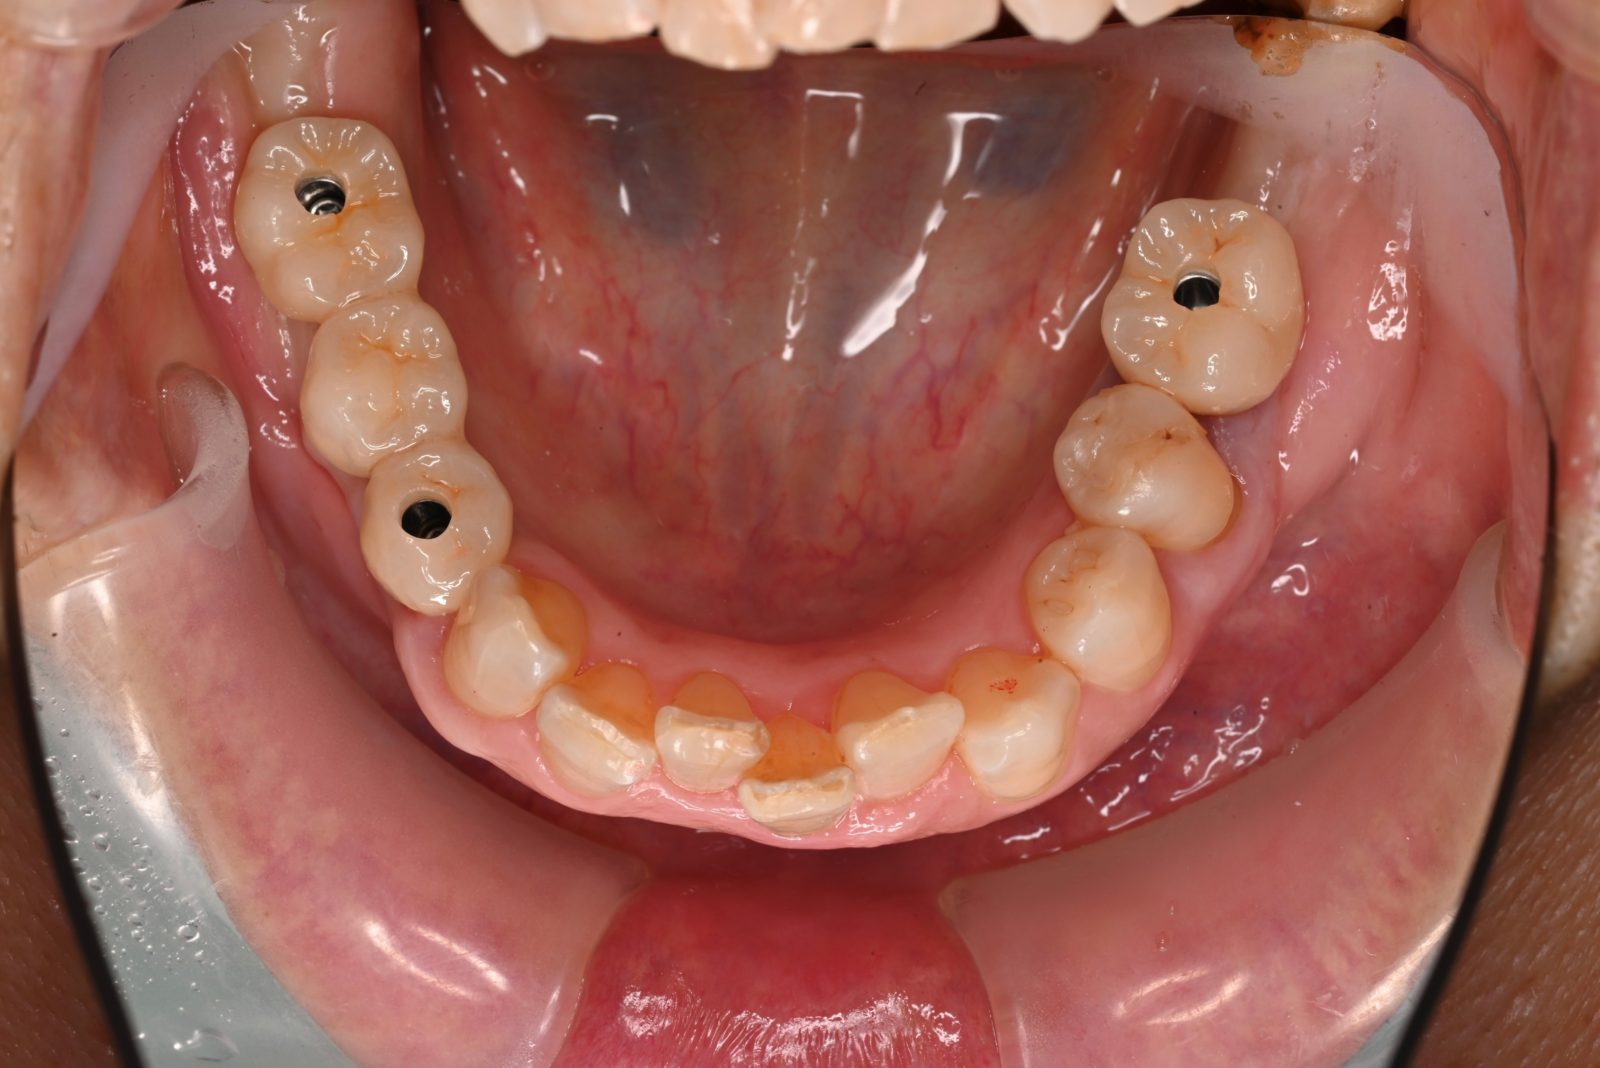

コンピュータインプラントで人為的ミスを最小限に

SMOPガイド

画像

人為的ミスを最小限に抑えるために、当院ではSMOPガイドを導入しています。SMOPガイドとは、インプラントを入れる位置をコンピュータでシミュレーションできるシステムのことです。

CTで撮影したデータを取り込むことで、どのように治療を行っていくべきなのかをコンピュータが計算します。神経や血管を傷つけないサイズのインプラントを選んでくれるのはもちろん、インプラントをどの位置にどのような角度で入れるべきなのかまで緻密に判断してくれます。